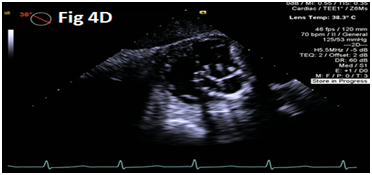

A 73-year-old female with mechanical mitral valve, tricuspid annuloplasty (32mm Edwards Physio Tricuspid incomplete ring) underwent Transcatheter Tricuspid Valve Replacement (TTVR) using off-label 29mm Edwards Sapien 3 (S3) Transcatheter Heart Valve (THV). Immediate post valve deployment, mild Perivalvular Leak (PVL) was noticed at the septal aspect (area of incomplete annuloplasty ring). Eighteen months later, patient presented with recurrent right heart failure and paracentesis due to severe tricuspid PVL (Figure 1A-C, Video 1). Percutaneous PVL closure under general anesthesia, Trans-esophageal Echocardiography (TEE) was performed. Via femoral venous access, defect was easily crossed with Agilis steerable sheath, multipurpose catheter and 0.035” glide wire. Despite recurrent attempts, wire came through the PVL but then traversed through open cells of S3 into the right ventricle (Figure 2A), confirmed with Armada 6mm balloon waist at the S3 cage (Figure 2B) (despite inflating 28mm Z med balloon inside S3 cage, Figure 2C). We decided to partially deploy the plug and assess valve function. Using 7.5F Asahi Eaucath multipurpose guide, a 12mm AmplatzerTM Vascular plug II (AVP II) was advanced through the defect. The ventricular disc was opened inside the S3 cage while body in the PVL defect (outside the S3 cage) and atrial disc on the atrial side of PVL (Figure 3A-B). With S3 function unaffected, no central leak and minimal gradient, PVL reduced to mild severity (Figure 4A-D, Video 2); the AVP II was successfully deployed (Figure 5). At 3-month follow up, there was an excellent symptomatic improvement (NYHA functional class I), with no heart failure re-hospitalization or paracentesis. Deployment of plug disc inside the valve frame is not recommended due to fear of interference with leaflet function and possible injury in long term. There was no immediate issue with the valve function in this case (due to space between the leaflet and frame of S3 and depends on size of plug used). Valve-in-Valve (S3-in-S3) would have certainly sealed all open cells treating this PVL but is more expensive option.

Figure 4 Post AmplatzerTM vascular plug II with mild residual PVL (4A), mildly elevated trans-S3 gradient (4B) and normal leaflet mobility of S3 (diastole 4C, Systole 4D).